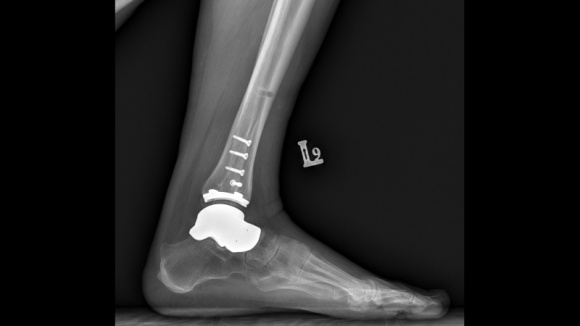

Jesienią odbyły się pierwsze w Polsce (i jedne z pierwszych w Europie) innowacyjne operacje stawu skokowego z wykorzystaniem hybrydowego wszczepu. Ich istotą było połączenie implantu kości skokowej z endoprotezą stawu skokowego. To rozwiązanie dla pacjentów z dużym uszkodzeniem kości skokowej.

Nowa proteza składa się z indywidualnie wykonanego, ?szytego na miarę? implantu kości skokowej, który zastępuje blokującą ruch w stawie skokowym i podskokowym zniszczoną kość skokową, oraz połączonego z nim elementu piszczelowego protezy stawu skokowego. W takim zestawieniu obie protezy tworzą wszczep hybrydowy, pozwalający na przywrócenie prawidłowego ruchu w stawie.